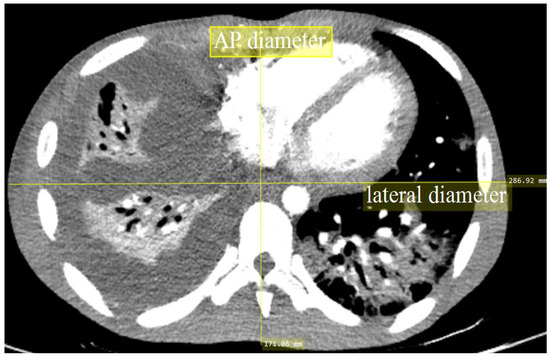

| Anteroposterior (AP) (cm) * | 21.68 ± 3.68 | 21.88 ± 2.71 | 21.80 ± 3.14 |

| Lateral (LAT) (cm) * | 33.46 ± 4.17 | 32.85 ± 3.53 | 33.10 ± 3.80 |